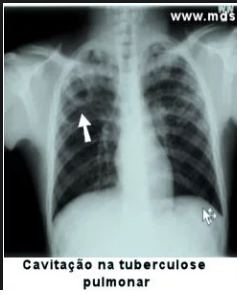

EM UM PACIENTE COM TUBERCULOSE PULMONAR, O QUE PODEMOS EVIDENCIAR EM UM RAIO-X DE PULMÃO?

- CAVITAÇÕES EM ÁPICE COM PRESENÇA DE AR

- CALCIFICAÇÕES

- DERRAME PLEURAL

- INFILTRADOS podem estar presentes